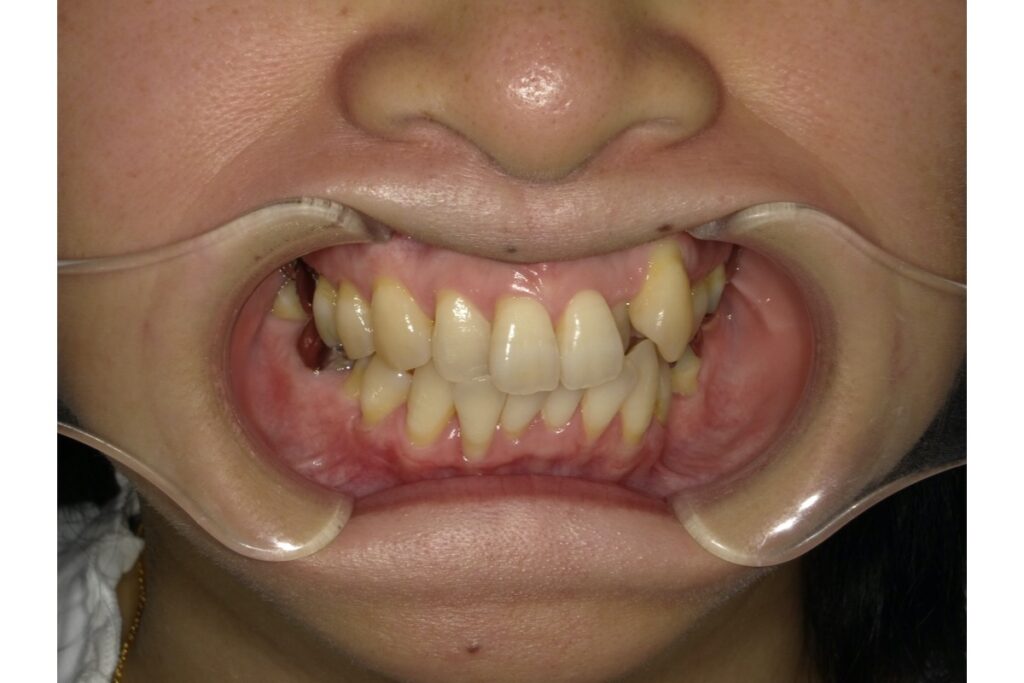

矯正前 -

矯正後

写真のようにもともと重なっていた歯や傾斜していた歯は、どうしても矯正力が強くかかるため歯肉が下がりやすい傾向にあります。